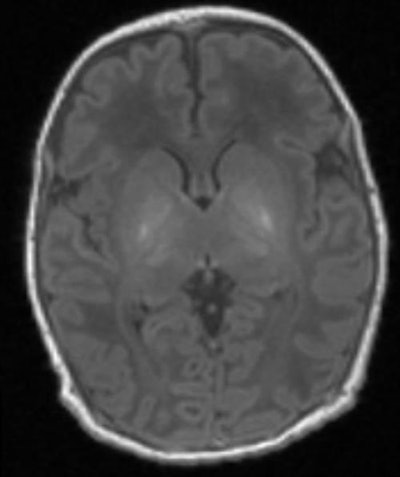

MR spectroscopy shows the brain of a baby with brain damage. There is abnormal brightness in the deep nuclei in the center of the brain. Image courtesy of Imperial College London."Proton MR spectroscopy should be a routine component of clinical MR protocols for infants with neonatal encephalopathy," wrote lead author Dr. Peter Lally from Imperial College London and colleagues. "This assessment is ideal for early prognostication and might provide promising surrogate outcome measures for multicenter clinical trials. If early-phase trials were to employ proton MRS measures, such as NAA concentration, this would greatly increase their power to detect important treatment effects while potentially reducing their duration by several years."